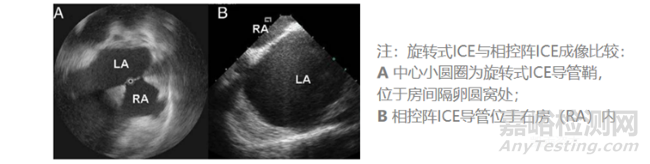

ICE使用5~12MHz的超聲頻率,理論最高分辨率可以達(dá)到0.1mm、且同時(shí)具有最高16cm的心內(nèi)穿透成像深度。常見(jiàn)的2D ICE導(dǎo)管分為單陣元旋轉(zhuǎn)超聲導(dǎo)管、電子相控陣列超聲導(dǎo)管兩類,目前后者在臨床上更為常用。目前ICE導(dǎo)管直徑為8~10Fr。

就2D ICE來(lái)說(shuō),相控陣ICE相比單陣元旋轉(zhuǎn)ICE具有以下優(yōu)勢(shì):更深成像深度、獲取多普勒血流彩超的能力。相控陣ICE因而在2D ICE當(dāng)中更受青睞。